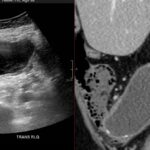

- Radiology Cases: Images with a to-the-point discussion highlighting the specific diagnostic criteria.

- Radiology Case of the Day Collection: Aunt-Minnie Board Cases for Rapid Review.

- Radiology Spotters: 700+ spot / “Aunt-Minnie” cases divided into sets of 10 each!